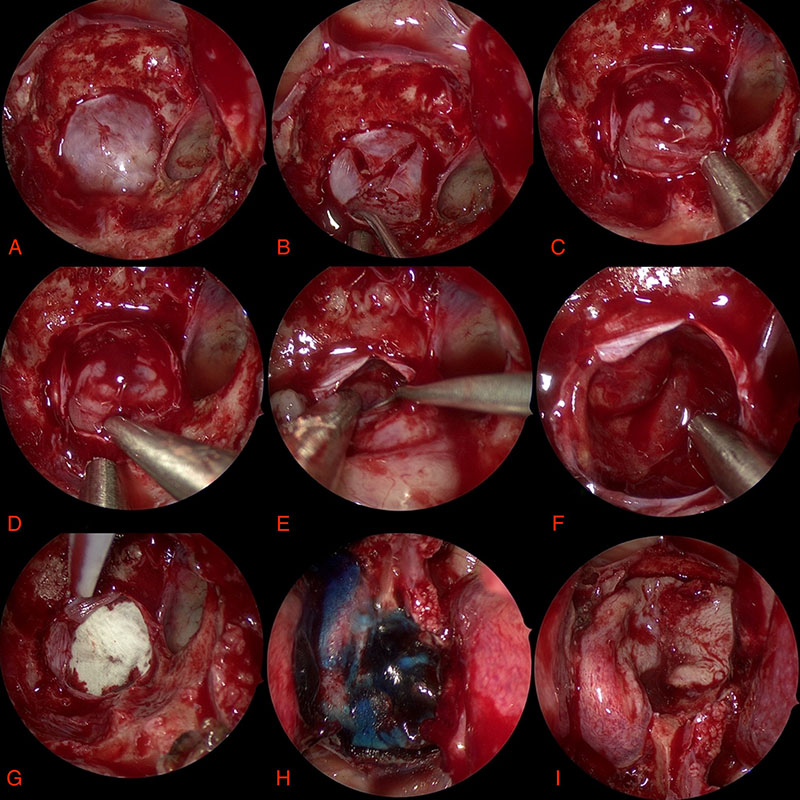

Surgical Photos

Here are some photos of the surgery looking down the microscope. Although it may appear bloody these photos are magnified a great amount. Remember the pituitary gland is around the size of two peas!

- Dura B. Opening dura C/D. Tumour E. After tumour removal F. Roof G. Patch H. Glue I. Flap